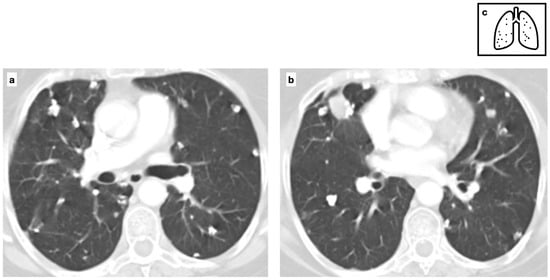

Pulmonary manifestations of amyloidosis involve two distinct patterns of lung parenchymal involvement. The nodular parenchymal type is the most common and is typically associated with localized AL amyloidosis. It is commonly characterized by discrete nodules, which may be single or multiple, heterogeneous in size, with smooth or lobulated margins and a subpleural predominance. Calcifications are present in approximately 50% of cases, often exhibiting a central or punctate pattern (Figure 7). While nodular cavitation is rare, lesions may slightly increase in size and number over time. Histopathologic confirmation is essential for a definitive diagnosis [23].

Figure 7.

Multifocal pulmonary nodules, variable in size, with smooth and lobulated contours, some of which are characterized by central calcification in a patient with biopsy-proven amyloidosis (a–c). The nodular parenchymal amyloidosis is commonly characterized by discrete nodules, heterogeneous in size, with subpleural predominance. Pattern of calcification (d).